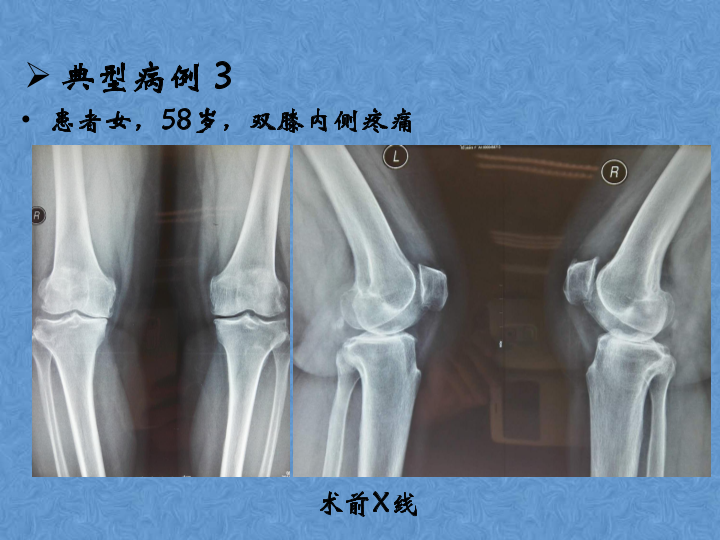

骨关节炎的阶梯治疗